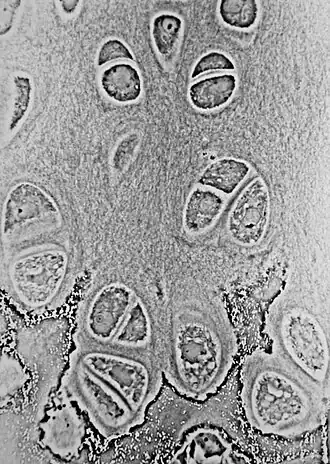

Light micrograph of an undecalcified epiphyseal plate that is displaying the hypertrophic zone with its typical chondrocytes, matrix and three zones: maturation (top), degenerative (middle) and provisional calcification (bottom).

The growth plate has a very specific morphology in having a zonal arrangement as follows:[8]

Epiphyseal plate zone (from epiphysis to diaphysis) Description

Zone of reserve Quiescent chondrocytes are found at the epiphyseal end

Zone of proliferation Chondrocytes undergo rapid mitosis under influence of growth hormone

Zone of maturation and hypertrophy Chondrocytes stop mitosis, and begin to hypertrophy by accumulating glycogen, lipids, and alkaline phosphatase

Zone of calcification Chondrocytes undergo apoptosis. Cartilagenous matrix begins to calcify.

Zone of ossification Osteoclasts and osteoblasts from the diaphyseal side break down the calcified cartilage and replace with mineralized bone tissue.